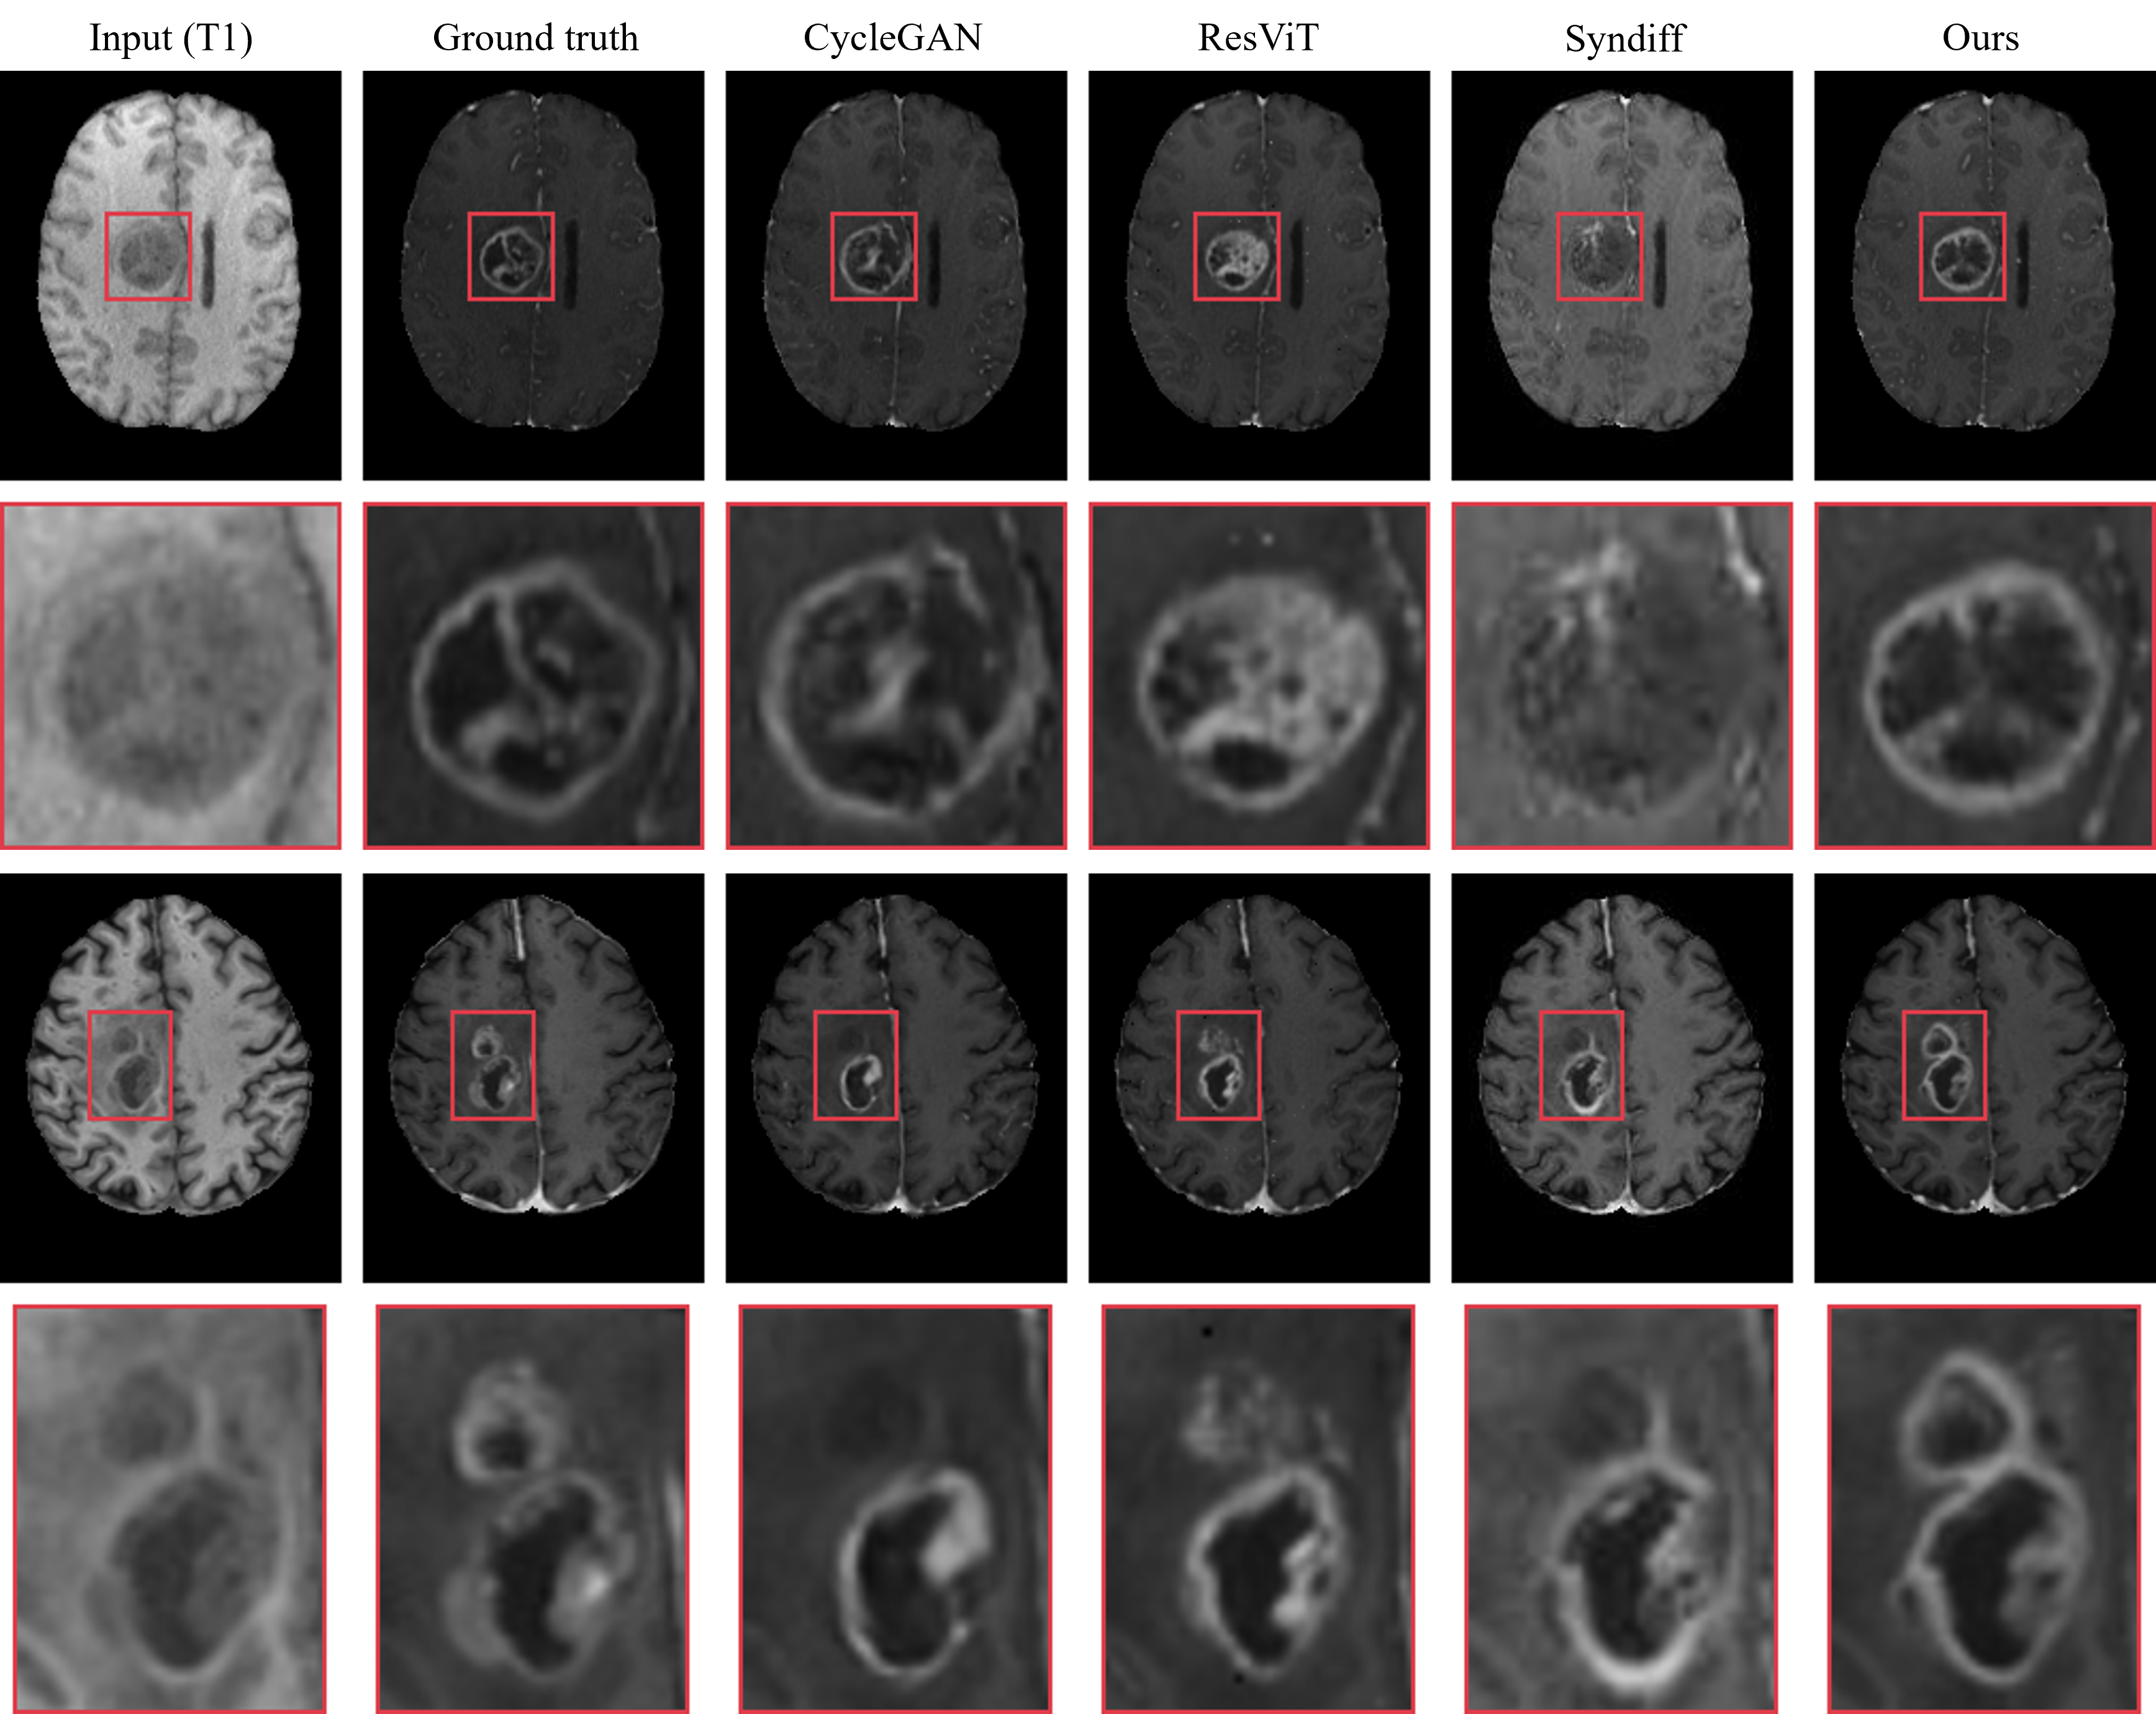

Figure 2: Visual comparison of synthesis results from all one-to-one models on the BraTS 2021 dataset. Each model takes T1 as input simultaneously to synthesize T1ce.

Fig. 2 and Fig. 3 show a comparison of the generated results between our method and CycleGAN, ResViT, and SynDiff in the single-input scenario. Clearly, our method synthesizes the most realistic details, with fewer artifacts and clearer tumor contours, which are critical for accurate diagnosis. While there is little difference in the healthy tissue synthesis across the different methods, our model outperforms the competing methods when it comes to lesion areas. It is noteworthy that during the testing phase, we did not use any prompts, yet our model still demonstrated strong attention to abnormal regions. Specifically, when only T1-weighted is used as input, as shown in the second-row example of Fig. 2, only our method does not miss small lesions. When T2-weighted is used as input, due to the more prominent lesions on the T2 image, as shown in Fig. 3, all methods do not miss any lesions. However, our model still achieves the most perfect detail synthesis and clear tumor contours, demonstrating significant advantages when handling lesions of different sizes.